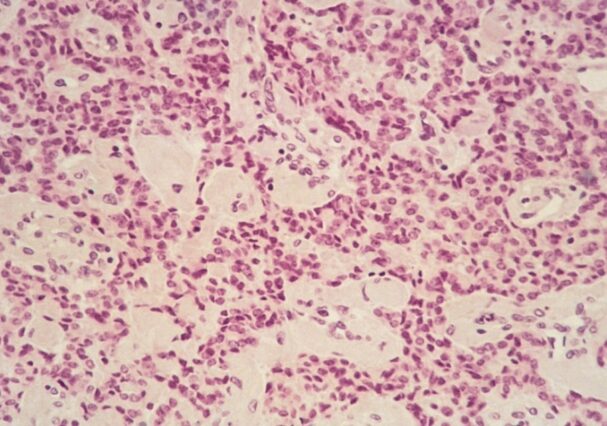

Cerca de la mitad de los gastrinomas son malignos, lo que significa que son cancerosos y tienen la capacidad de propagarse a otras partes del cuerpo, particularmente al hígado, donde suelen formar metástasis. Debido a esta tendencia metastásica, los gastrinomas pueden ser difíciles de tratar en etapas avanzadas.

En cuanto a su localización, los gastrinomas pueden encontrarse en el duodeno en aproximadamente el 49% de los casos, en el páncreas en alrededor del 24% de los casos y en los ganglios linfáticos en aproximadamente el 11% de los casos. Su ubicación en el páncreas o el duodeno puede hacer que el diagnóstico sea desafiante, ya que estos órganos son difíciles de visualizar con los métodos de imagen convencionales.